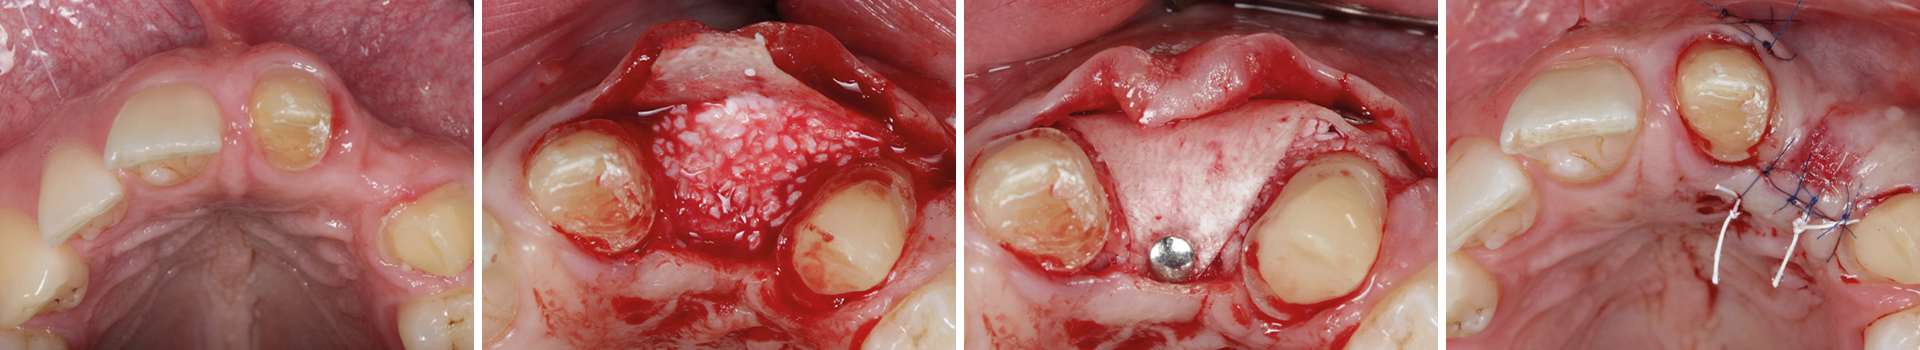

Abbildung 3

Nach Bildung eines Mukoperiostlappens wird mit der Bone Lamina die bukkale Lamelle rekonstruiert. Die Lamina wird mit Titanpins befestigt.

Abbildung 4

Der Defekt wird mit mp3® augmentiert.

Abbildung 5

Lamina so ausgeschnitten, dass das mp3® krestal abgedeckt werden kann. Auch hier wird ein Titanpin angewandt.

Abbildung 6

Das Augmentat wird mit einer Kollagenmembran abgedeckt.

Abbildung 7

Der Weichgewebsverschluss muss spannungsfrei erfolgen. Einsatz von mikrochirurgischen Techniken.